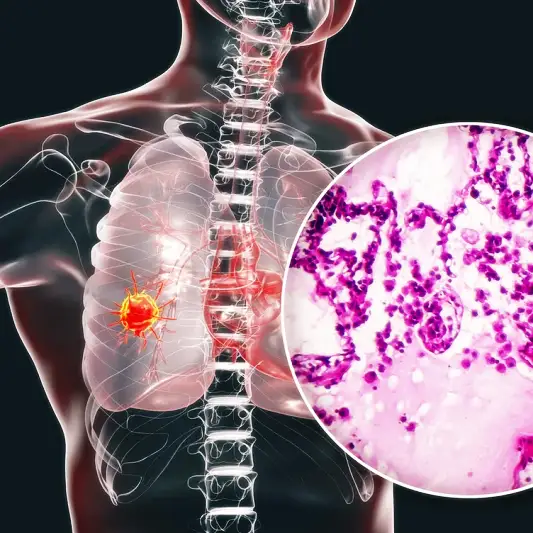

폐암 수술은 환자들에게 중대한 물리적 및 정신적 영향을 미칩니다. 수술 후 이러한 영향을 완화하고 성공적인 회복을 위해서는 알맞은 관리와 후송 기간이 필요합니다.

첫째로, 수술 후에는 상처의 치유와 감염 예방을 위해 적절한 처치가 필요합니다. 이는 정기적인 상처 관리 및 안티바이오틱의 사용을 포함합니다.